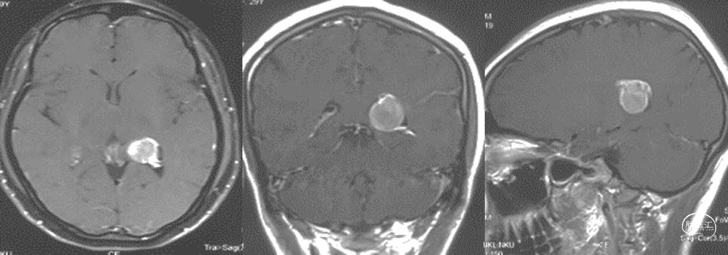

术后复查

砂砾型脑膜瘤,WHO 1级。

本例脑膜瘤患者,经机器人辅助神经内镜下,完成侧脑室肿瘤全切除,实现了脑膜瘤精准微创治疗,同时也对神经功能起到良好的保护。